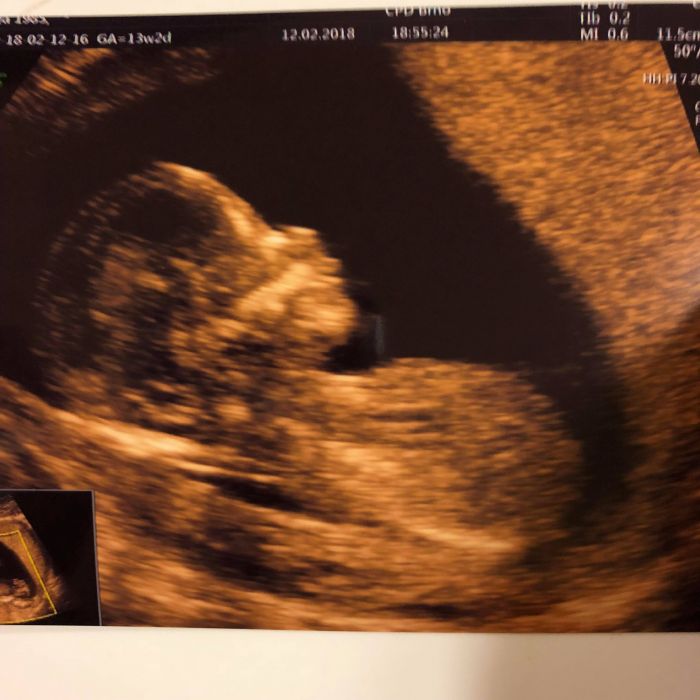

[1061385] ale su krasne tie nase detatka

No, miminka mame krasny, je to uzasny, jak se hybalo a tak